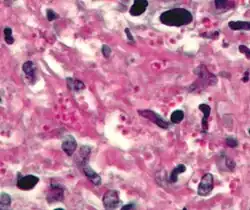

Histoplasma in a granuloma. PAS diastase stain.